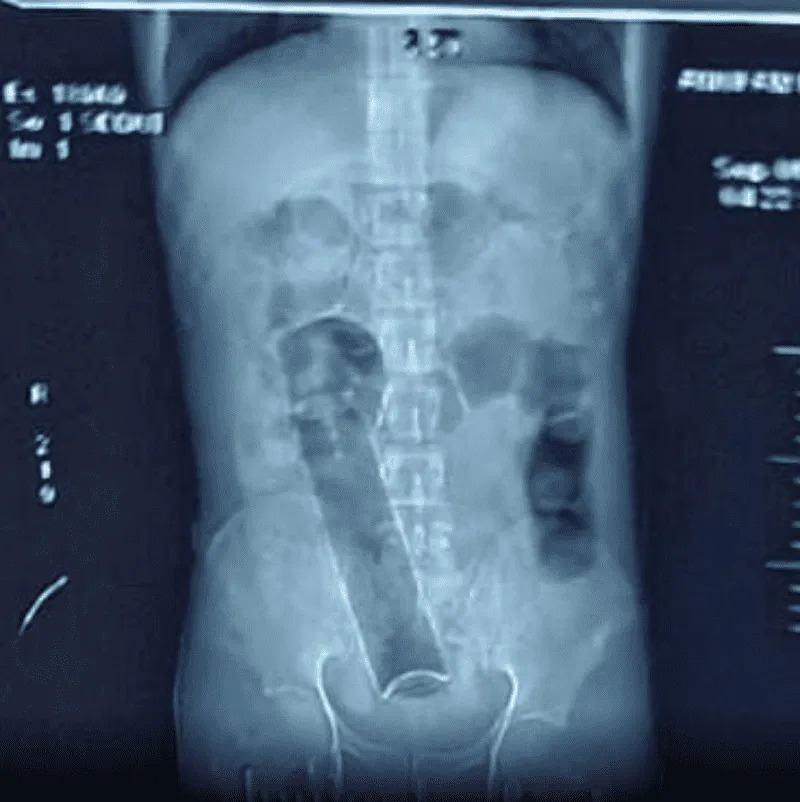

Después de revisar los rayos X, los especialistas se dieron cuenta de que había un recipiente en el interior del estómago del paciente de unas siete pulgadas y media (Poco menos de 20 cm), por lo que decieron internalo y operarlo.

Posterior a que los profesionales de la salud localizaran el objeto en el cuerpo del hombre, fue llevado al quirófano del departamento de emergencias de la Universidad de Ciencias Médicas de Teherán, donde extrajeron exitosamente el frasco.